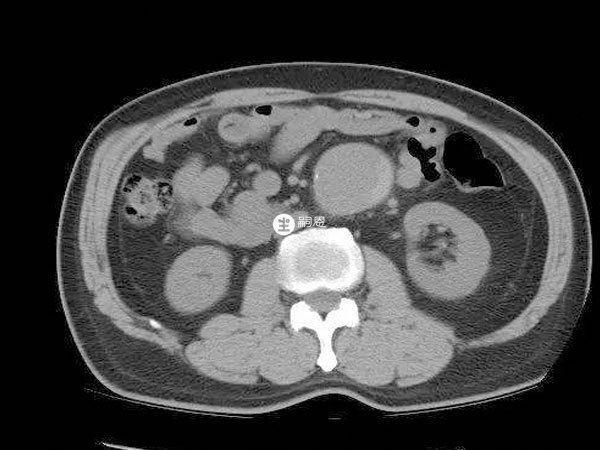

我和老公備孕好幾年懷不上,就打算做試管備孕,結果前期檢查的時候發現我有腹主動脈瘤,醫生讓我先治療,等病症緩解後再做進一步打算,我真的擔心這樣會做不了試管,想下有腹主動脈瘤能正常做過試管嬰兒嗎?會不會對胚胎移植造成影響?腹主動脈瘤對生育功能沒有明顯不良的影響,所以是能做試管嬰兒助孕的,對胚胎移植也不會有影響。不過在試管前最好是做腹主動脈瘤手術進行治療,在術後三個月之後再考慮備孕的相關事宜。手術一般是採取的開放式人工血管置換術和介入下支架植入術,這幾種方式對後期生孩子都不會造成太大的影響,手術治療後就可以正常備孕。

腹主動脈瘤是血管外科常見疾病,如果不進行治療腹主動脈管腔會持續增大,血管破裂的風險也會逐漸增高,一旦確診一定要及時手術治療。要不然一旦腹主動脈瘤破裂,會造成出血的現象,嚴重的還會危及生命健康,所以腹主動脈瘤最好是解除危險之後再妊娠會比較好。